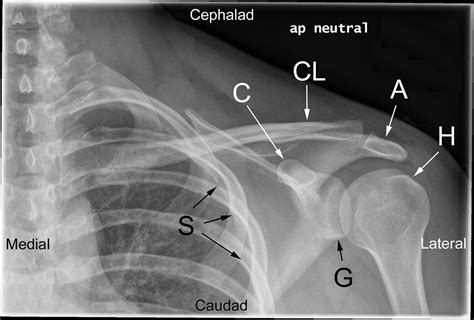

Diagnosing posterior shoulder dislocation involves a combination of physical examination and imaging tests. The diagnostic process typically includes:

• Physical Examination: A healthcare provider will assess the shoulder for deformity, swelling, and range of motion.

• Imaging Tests: X-rays are the primary imaging tool used to confirm the diagnosis. Additional tests such as CT scans or MRIs may be ordered to evaluate the extent of the injury and any associated damage to surrounding tissues.